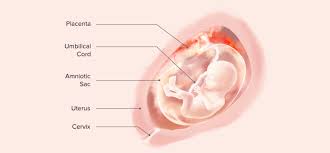

Real Life 17 Weeks Fetus Pictures : 17 Weeks Pregnant Babymed Com - Where is the baby located at 17 weeks pregnant?. Our content is doctor approved and evidence based, and our community is moderated, lively, and welcoming. At this stage, your baby might measure just over five inches long, crown to rump, and weigh about five ounces. Big bellies at 17 weeks 3 days pregnant. Over 40% of all abortions are done after 9 weeks. By 29 to 30 weeks, a growing baby has matured a lot.

You can see hands, feet, eyes, and ribs. At 17 weeks pregnant, your baby is putting on some fat and gaining muscle. Baby's eyes are opening and she's gaining weight. Total length 17 inches.weight, 3 pounds. This photo shows a baby at 16 weeks of gestation during the second trimester of pregnancy.

Suction aspiration, or vacuum curettage, is the abortion technique used in most first trimester abortions. At this stage, your baby might measure just over five inches long, crown to rump, and weigh about five ounces. The average weight of a baby is about 135 g. When you're 17 weeks pregnant, the fetus is about the size of a pear! What to do in week 17. The baby begins to form a substance called meconium, which is the first bowel movement. Tissues including bones and muscles continue to form. At week 17 the fetus is actively gaining weight and growing.

Pregnancy baby womb baby in womb teratogenicity illustration fetal development week 9 baby unborn pregnant of twins pregnancy week 4 baby in uterus embryo baby womb. I just saw the picture after 3 years and looked up fetal images at 8 weeks and somehow stumbled upon this tragic video. At 15 weeks, roman and other preborn children just need a handful of weeks to grow in their mother's wombs until they reach viability. Suction aspiration, or vacuum curettage, is the abortion technique used in most first trimester abortions. See fetus stock video clips. After meeting while praying on the sidewalk of an abortion facility, edward garcia, a single father of two, and i, a single mother of two, married. And the height is about 12 cm. When life published lennart nilsson's photo essay drama of life before birth in 1965, the issue was so popular that it sold out within days. Miscarried at 13 weeks and 4 days, baby nathan isaiah's short life inside the womb affirms the humanity of the preborn at the earliest stages of life. Baby development at 17 weeks. This photo shows a baby at 16 weeks of gestation during the second trimester of pregnancy. Week 17 of your pregnancy. Our content is doctor approved and evidence based, and our community is moderated, lively, and welcoming.

The baby begins to develop translucent skin. Pregnancy baby womb baby in womb teratogenicity illustration fetal development week 9 baby unborn pregnant of twins pregnancy week 4 baby in uterus embryo baby womb. Mother's powerful photos of baby miscarried at 16 weeks show humanity of preborn children. The size of the fetus at 17 weeks pregnant. Beyond the eighth week of pregnancy, the embryo is called a fetus. Incredible real photos of the human developing in the womb. Length, 10 3/4 inches, crown to rump; This photo shows a baby at 16 weeks of gestation during the second trimester of pregnancy. Suction aspiration, or vacuum curettage, is the abortion technique used in most first trimester abortions. Big bellies at 17 weeks 3 days pregnant. The average weight of a baby is about 135 g. Week 17 of your pregnancy. The mirror reports brooklen nicole spent more than 24 weeks in the womb, but a problem with her placenta.